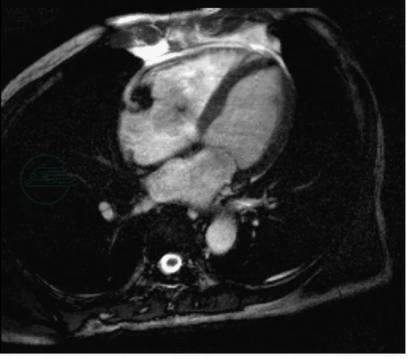

(5)联合瓣膜损害

MRI和CT(多排螺旋CT和电子束CT)能显示瓣膜损害的直接与间接征象,尤其是MR电影成像,无需注射对比剂,显示多个瓣膜受损情况,对瓣膜狭窄和关闭不全的诊断相当可靠(图3)。

图3三尖瓣关闭不全

MR电影成像显示收缩期三尖瓣口的反流低信号

引自:实用放射学.第4版.ISBN:978-7-117-28542-1.主编: